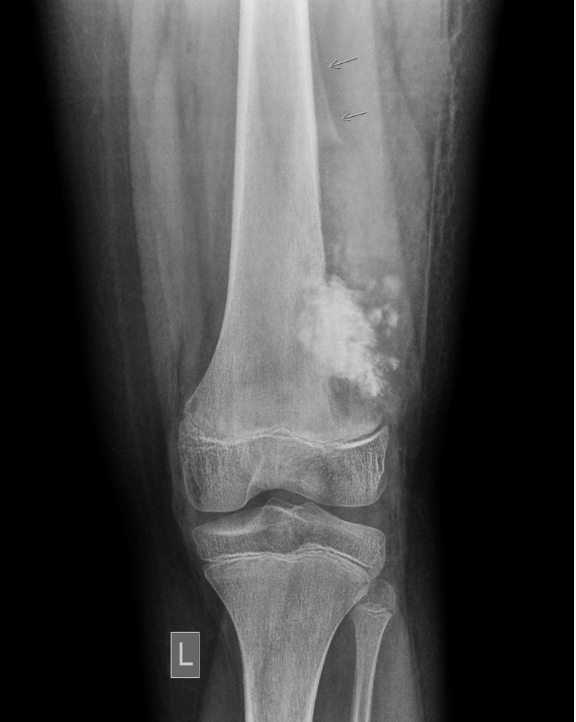

Q

What is this?

A

Osteosarcoma